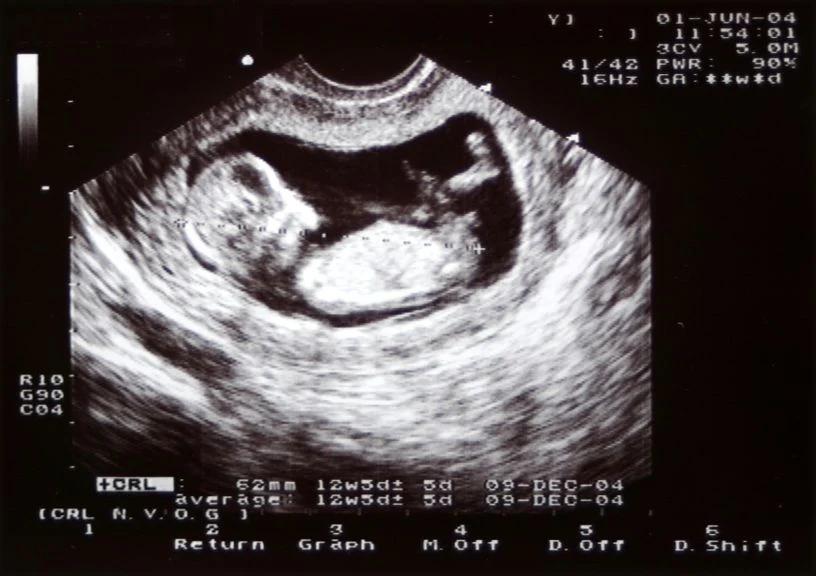

- 2D-Ultraschall: Der 2D-Ultraschall ist die häufigste Art von Ultraschalluntersuchung. Er zeigt das Baby in Schwarzweiß auf dem Bildschirm.

In der Regel werden drei Ultraschalluntersuchungen während der Schwangerschaft durchgeführt:

- Zweite Ultraschalluntersuchung (zwischen der 1und 2Schwangerschaftswoche): Diese Untersuchung dient zur Beurteilung der Entwicklung der Organe des Babys und zur Feststellung des Geschlechts, falls gewünscht.